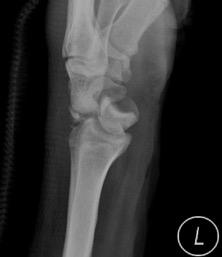

På tisdagen genomfördes tre klassis ka workshops i frakturkirurgi. Magnus Tägil, SUS Lund, höll med stöd av Zimmer Biomet en kurs i handleds frakturer där volar plattfixation lärdes ut. Deltagarna var engagerade och den uppskattade föreläsningen följdes av en gruppdiskussion som engagerade hela auditoriet. ST-läkaren Maria Ström, SUS, kommenterar ”Det var väldigt bra att få öva på osteosyntes i lugn och ro”. I grannsalarna pågick märgspikning under ledning av Per Bosemark, SUS Lund. Det fanns ett flertal stationer att välja mellan beroende på vilken kunskapsnivå deltagarna befann sig på. Workshopen bestod av antero- och retrograda femurspikar samt tibiaspi kar. Mattias Callreus, SUS Malmö, höll i en workshop i fotfrakturer som innehöll fixation av mellanfotsfrakturer inklusive LisFranc-skada.